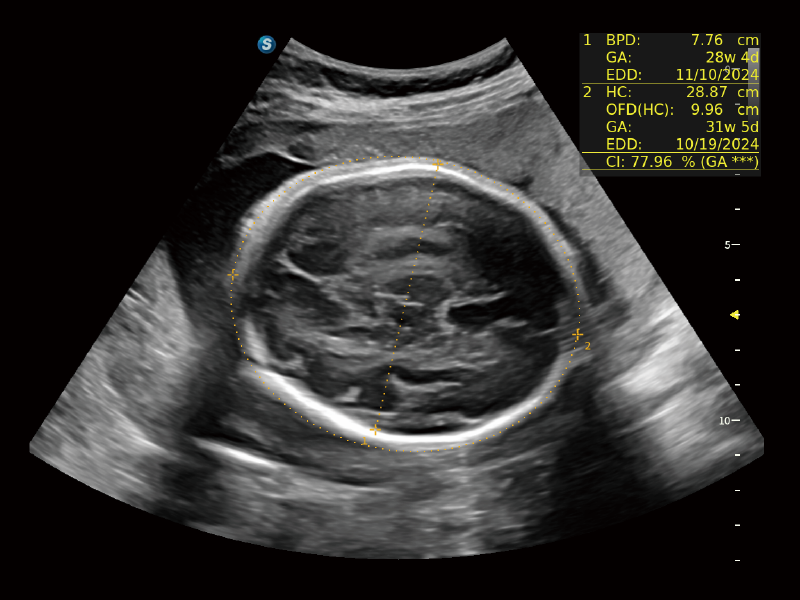

Image quality always lies at the core of definitive clinical outcomes. The P80 Elite introduces evolutional transducers with excellent 2D image clarity and color sensitivity for more confident assessment in anatomy and pathology.

Auto NT with HD-Zoom

S-Fetus 5.0